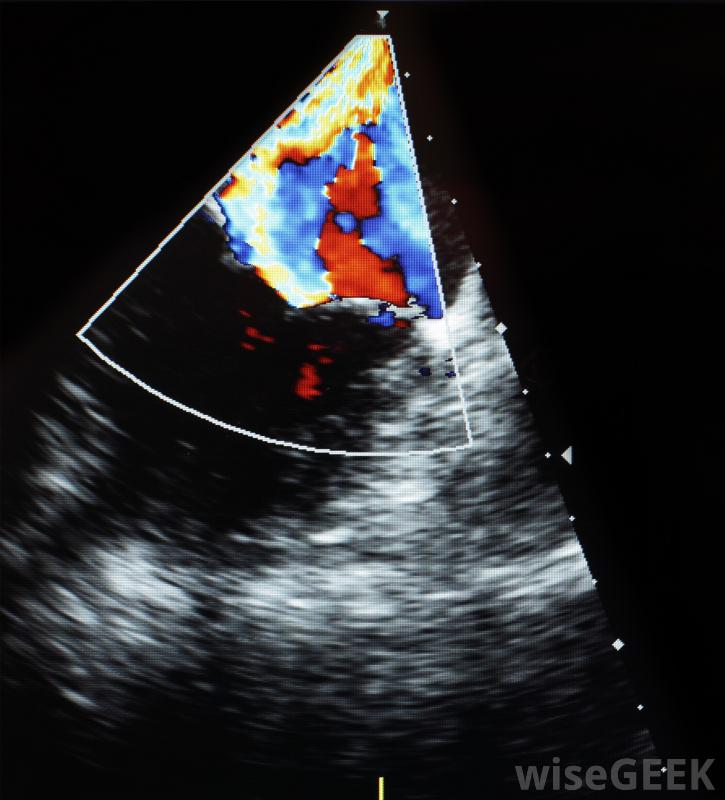

超聲心動圖是一種診斷測試,它使用聲波來產生心臟的圖像。它可以用來確定你的心臟是否在泵血,以及是否存在任何結構異常。這些圖像可以用來檢測你的心肌和瓣膜的不同類型的問題。你的結果應該列出幾個一些信息,包括你的心臟大小,泵血強度,以及在測試過程中發現的任何異常。

超聲心動圖結果將提供有關心臟泵送強度的信息。該測試可以查看特定的測量值,例如每次心跳時從充滿的心室中泵出的血液量,或者一分鐘內泵入心臟的血液量。測量結果被列為射血分數,或EF。正常EF結果在55%到65%之間。低于45%的數值表明泵送強度有所下降,而低于30%的數字則表明心臟功能明顯下降。當心臟無法泵出足夠的血液來滿足身體需要時,可能會發生心力衰竭。

超聲心動圖使用高頻聲波傳輸到心臟檢測心臟的形狀、大小和運動。

心臟缺陷也可以在超聲心動圖上顯示出來。通常,心臟缺陷在出生時就存在,盡管有些會在以后的生命中出現。超聲心動圖可以幫助醫生確定你是否有結構異常,例如心臟和主要血管之間的異常連接。該測試還可用于監測心臟發育和在出生前診斷缺陷。